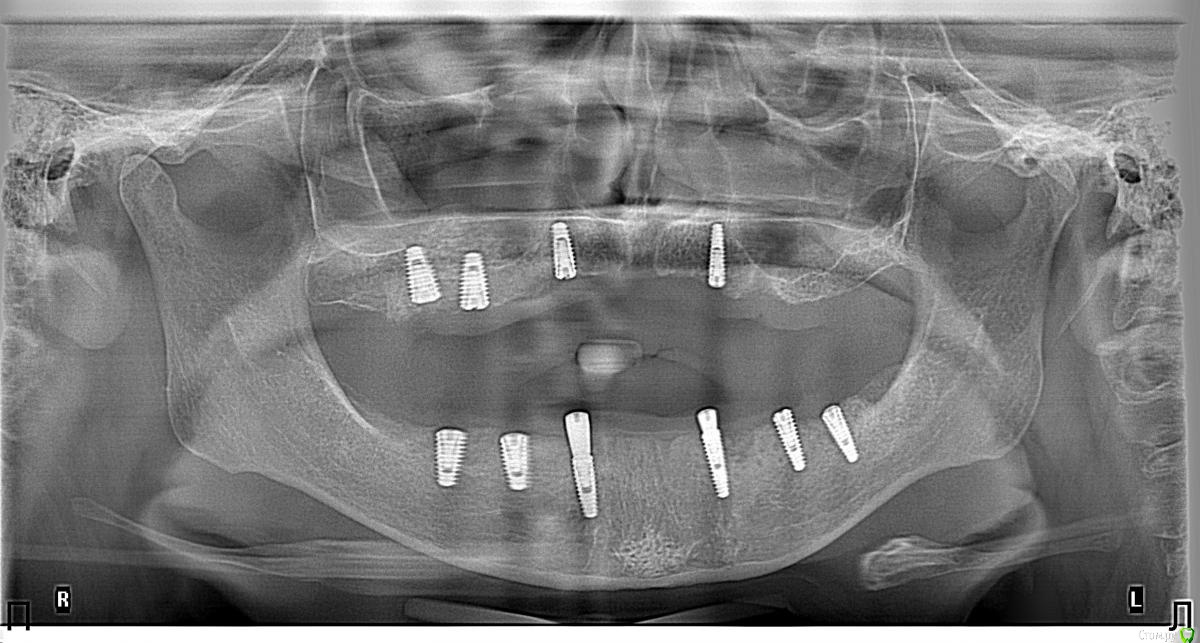

Борис80 Опубликовано 13 февраля, 2018 Поделиться Опубликовано 13 февраля, 2018 Слева виден средний имплант, его бы поглубже... витки выше уровня кости... КТ с имплантами нет? Я бы ещё подождал... уже через месяц считайте импланты будут интегрированы...временный съемный без нагрузки на импланты уже сейчас можно изготовить, если на него пациентка согласна... 1 Ссылка на комментарий

Nitrino1 Опубликовано 21 февраля, 2018 Автор Поделиться Опубликовано 21 февраля, 2018 Коллеги, сделали КТ, картина следующая. Вопрос, как рекомендуете, переустановить на то же самое место только глубже или же все таки менять место?ССТ все таки рекомендуете сделать:? Ссылка на комментарий

Nitrino1 Опубликовано 28 февраля, 2018 Автор Поделиться Опубликовано 28 февраля, 2018 Коллеги, отписываюсь как все произошло)Для начала мы сделали синус на верхней челюсти, в прошлый раз не получилось, так как случайно порвали мембрану шнайдера. Тогда запихали туда ПРФ и закрыли. В этот раз открыли, там уже костная пластинка и мембрана зажила (прошло всего 3-4 недели). Вообщем сделали синус, закрутили 2 болта и зашились. Теперь самое интересное, перешли на нижнюю челюсть к проблемной зоне. Если вы заметили на снимке, видно было 2 резьбы импланатата. Так вот, их уже не было видно, они были закрыты костной пластинкой тонкой. Все равно я выкрутил оба импланата, запаха не было, но выкрутились довольно таки легко. Заглубился, и поставил новые, прф и все дела как полагается, теперь ждем. Ссылка на комментарий